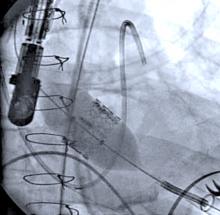

In the cardiac cath lab, the use of iodinated contrast in both diagnostic and PCI procedures is commonplace. The effects of iodinated contrast on renal function have been known and researched. However, conversations are ongoing around best practices and standards of care regarding contrast management and treatment for those with higher risk factors, like compromised renal function. Participate in this webinar to gain insight on the topic of contrast-induced kidney injury and how one could approach contrast management in modern PCI with use of the ACIST CVi Contrast Delivery System.

Preventing contrast induced nephropathy and managing patients with chronic kidney disease remain major challenges in the cardiac catheterization lab. In recent years, contrast supply shortages have presented a new challenge to care delivery. When considering these challenges, and as quality metrics in our labs face more scrutiny, there are existing technologies and best practices such as a variable rate contrast delivery systems and HD IVUS that can be used to manage workflow and improve patient outcomes.

The ACC Interventional Council’s recent statement recommending that intracoronary imaging be a routine part of clinical practice further reinforces the need for adoption of intracoronary. Using a case-based approach, the faculty will demonstrate how to use the ACIST CVi contrast delivery system, HDi high definition IVUS and diagnostic and post-PCI physiologic assessment to reduce contrast usage, improve AKI rates and deliver optimized patient outcomes.